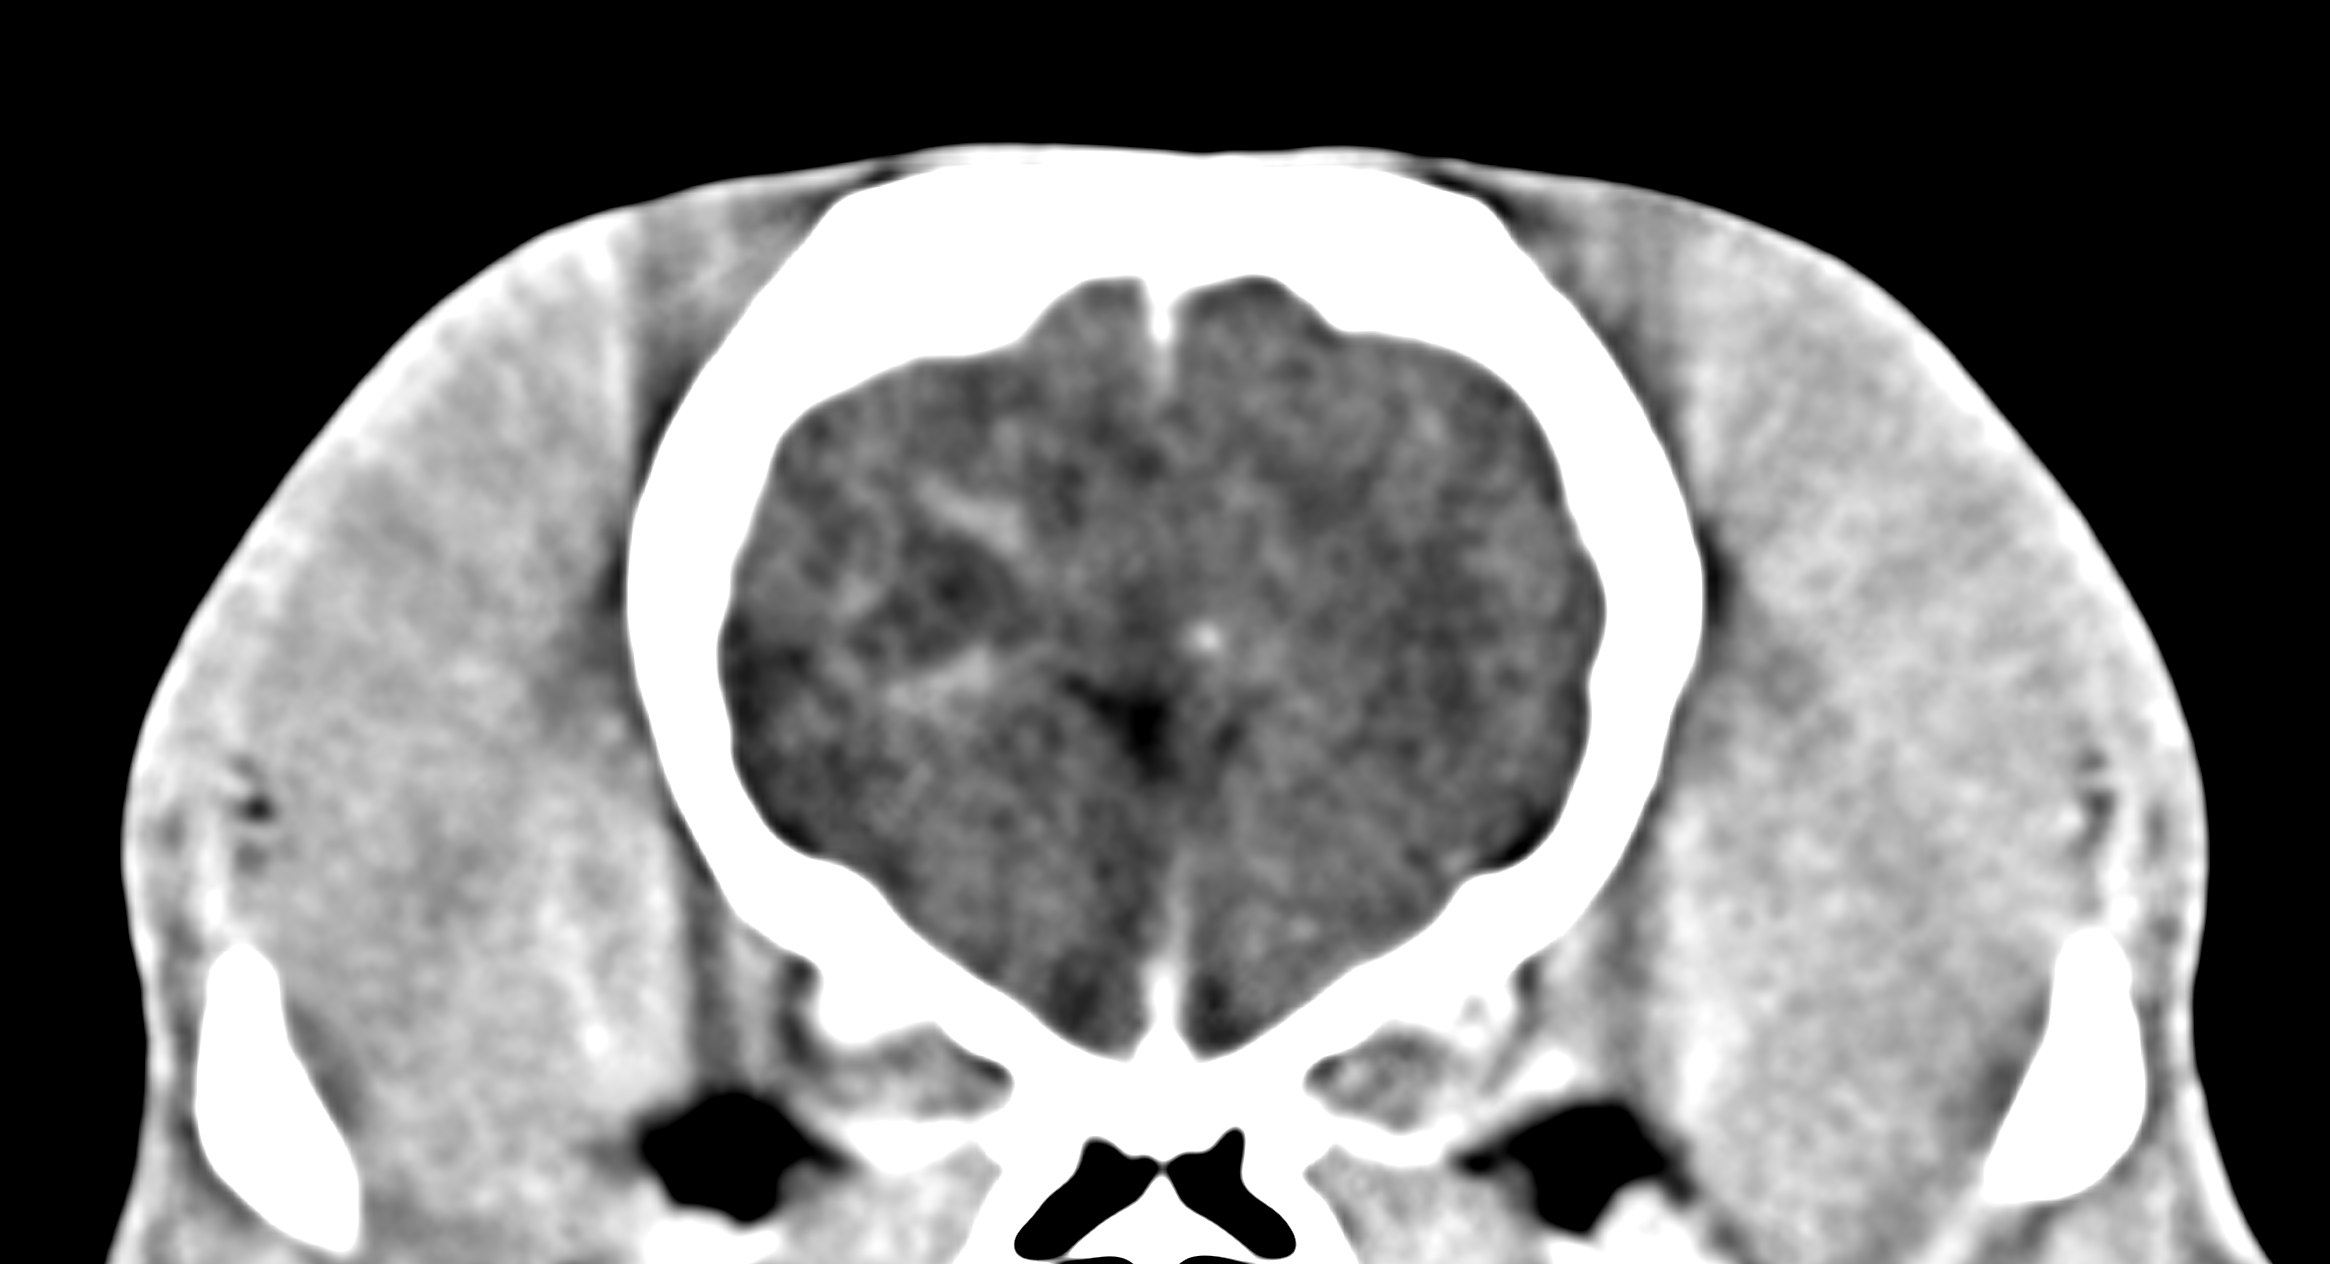

Advanced imaging and specialist investigations are often required to establish a neurological diagnosis. These may include CT, MRI or cerebrospinal fluid sampling and are arranged at trusted partner hospitals with appropriate facilities for neurological patients.